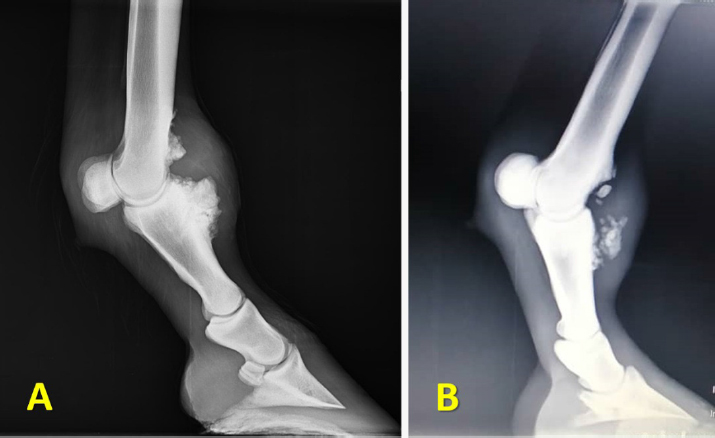

The radiological examination revealed a new bone formation involving the dorso-proximal aspect of P1 (Fig. 2A and B). The size of the newly formed bone was variable among cases. No other abnormal radiographic findings were noted in the horses. In two cases, the exostosis was extended proximally to include the dorsal aspect of the distal extremity of Mc3 (Fig. 3A). In one of the two cases, there were multiple fragments in both P1 and Mc3 exostosis (Fig. 3B).

Fig. 2. Distal limb radiographs for Sarj horses presented with hard swellings involving the dorsal aspect of the fetlock region. (A) Lateromedial view of forelimb fetlock shows small new bone formation on the dorso-proximal part of P1. (B) Lateromedial radiograph for another horse with a larger dorsal P1 exostosis. P1: first phalanx.